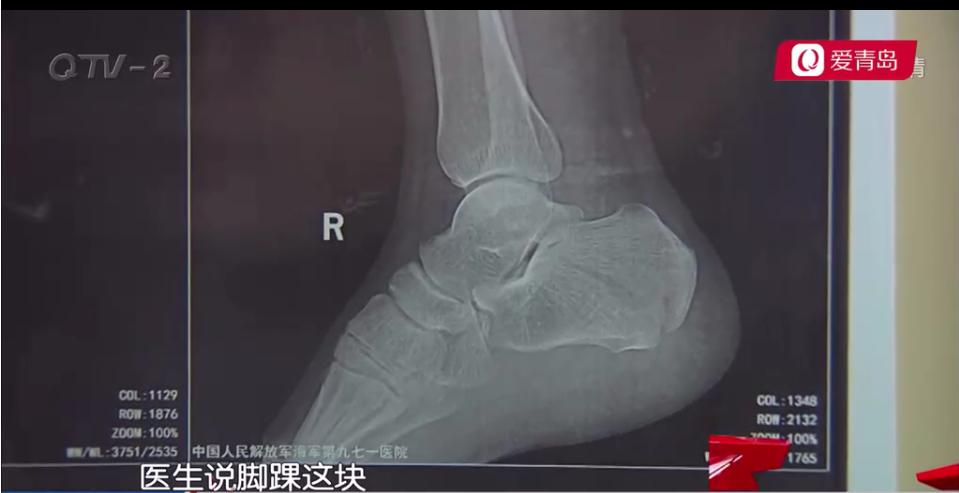

李新江说,当时自己踩在一米多高的架子上,可能是架子不稳,自己失足摔落,医院诊断为右足跟骨粉碎性骨折。